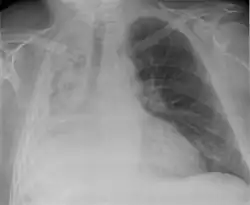

Niedodma (łac. atelectasis) – bezpowietrzność miąższu płucnego spowodowana zamknięciem oskrzela doprowadzającego powietrze do określonego obszaru miąższu płucnego lub uciskiem (niedodma z ucisku) będącym skutkiem obecności płynu w jamie opłucnowej lub innej zmiany uciskającej na miąższ płucny.